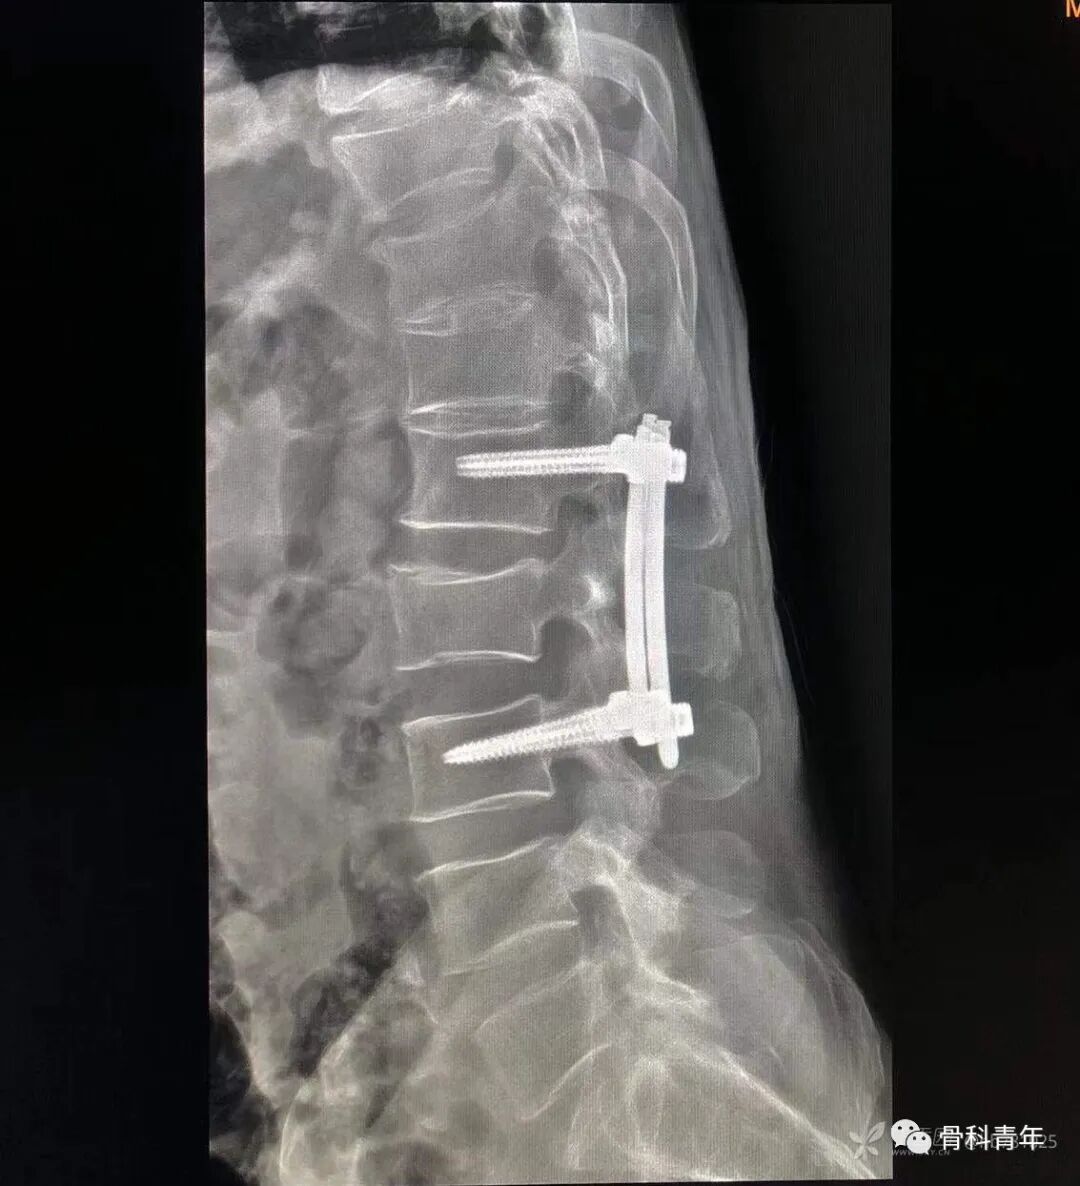

18.经皮椎弓根钉